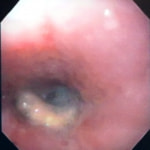

症例:炎症性ポリープ M.ダックス 10歳 オス

主訴:8ヶ月前から便が細くなり、血が混じることがある。その他、元気・食欲等、一般状態は良好。

経過:超音波検査にて直腸壁の肥厚(5㎜)が認められた。また、直腸検査で直腸全周に結節状病変を触知し、出血も確認された。消炎剤、抗生剤、整腸剤による治療への反応が長期的に悪いため、生検も含めた内視鏡検査を実施した。

内視鏡検査:肛門付近の直腸全周に、炎症および出血を伴う結節状病変を多数認めた。

病理検査:直腸の病変は、良性の非腫瘍性病変の一つである“炎症性ポリープ”と診断された。

診断後経過:炎症性ポリープは多発する傾向や腫瘍に転化する可能性があるため、消炎剤、抗生剤、整腸剤による内科療法を継続しながら、現在プルスルー法による外科的摘出術を検討中。